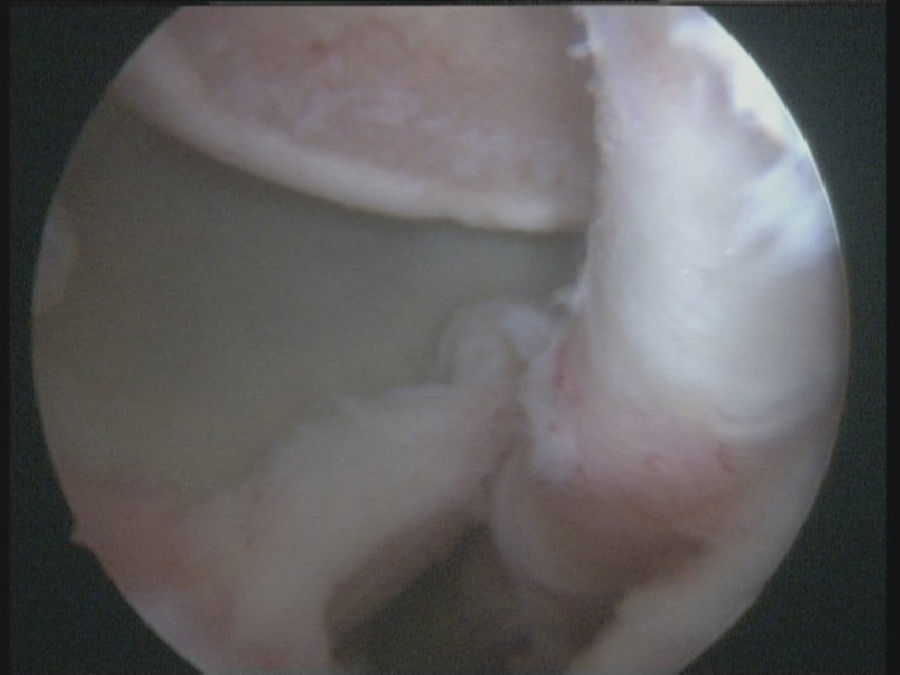

Fue trasladado al hospital más próximo y valorado por un médico de urgencias; se le realizaron radiografías que se consideraron normales y se diagnosticó una contusión de hombro y se remitió a su médico de atención primaria para control de la evolución. Tras 6 semanas el paciente no evolucionaba bien y se remite a consultas externas de traumatología. El paciente presentaba dolor y gran limitación funcional, con una flexión de 80°, abducción de 70° y 0° de rotación externa, con artrofia del deltoides y del infraespinoso y con actitud antiálgica en rotación interna. En la radiografía simple se diagnosticó una luxación posterior de hombro y se solicitó una RMN urgente, que mostraba una luxación posterior bloqueada del hombro derecho con un defecto óseo anterior en la cabeza humeral y una lesión del labrum posterior (fig. 1A). El paciente se intervino a los 2 días de la visita en consultas externas de traumatología.

Técnica quirúrgicaBajo anestesia general y locorregional (bloqueo interescalénico), se intenta reducir el hombro de forma cerrada. En caso de no conseguirlo se coloca al paciente en decúbito lateral con tracción de unos 5kg y, siguiendo la técnica descrita por Verma5, se introduce un «Wissinger» por el portal posterior estándar, el que empleamos para la artroscopia de hombro. Con el «Wissinger» a través del portal realizamos tracción de la cabeza humeral hacia lateral, apoyándonos en la cápsula y en la parte posterior del manguito, no en el hueso. Habitualmente con esta maniobra conseguimos introducir la cabeza humeral en la glenoides y podemos pasar a realizar la artroscopia de hombro. En caso de no conseguir una reducción, pasaríamos a realizar una reducción abierta con el paciente en posición de silla de playa y con una vía de abordaje anterior al hombro. Con el hombro reducido se realiza la artroscopia de hombro. Se emplean los portales posterior, anterosuperolateral, anterior, portal de Wilmington y portal posteroinferior. Se estudia la lesión de Hill-Sachs inverso, la relación con el tendón del subescapular y la lesión del labrum posterior (fig. 2, figs. 3 y 4), el resto del labrum y el manguito de los rotadores. Hay que limpiar bien la articulación, extirpar todo el tejido fibroso, liberar el labrum posterior de las adherencias a la glena, preparar el lecho óseo de la glena antes de colocar los implantes (en el caso 1 se emplearon 2 implantes Lupine BR [DePuy Mitek, Raynham, MA], y el caso 2 con un Gryphon BR [DePuy Mitek, Raynham, MA] cargado con doble sutura), realizar la reconstrucción capsulolabral con un pasador directo o indirecto, anudar y cortar las suturas. Una vez reparadas las lesiones soltamos el brazo del sistema de tracción y comprobamos la relación de la cabeza humeral, del defecto óseo anterior con la glenoides, al hacer rotaciones del hombro (sobre todo si hay riesgo de «enganche» con la rotación interna), y decidimos si fijamos el tendón del subescapular en el defecto óseo humeral anterior, tal y como describió Krackhardt6.